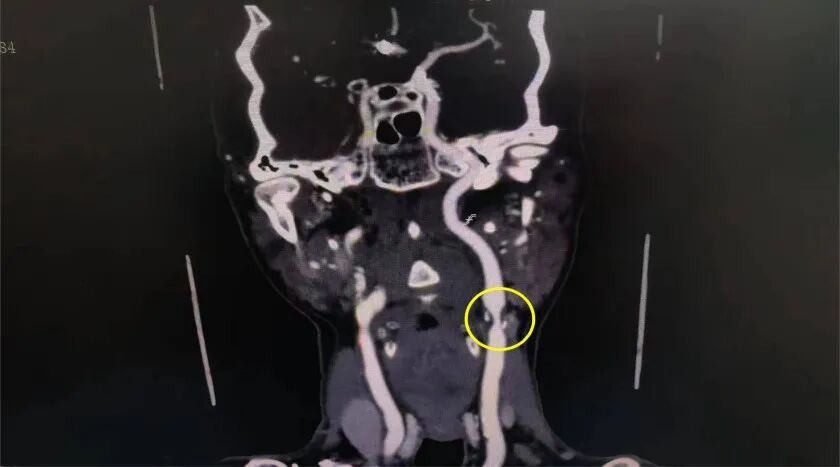

患者是一名70歲高齡的男性病者,既往有腦梗塞病史,入院前反復出現(xiàn)一側肢體乏力(大腦缺血癥狀),CTA提示左側頸內動脈開口段斑塊形成并重度狹窄,造影提示狹窄達90%,有明確行頸動脈內膜剝脫術的手術指征,如不盡快手術,頸動脈內膜斑塊將會完全堵塞頸動脈管腔,患者隨時有出現(xiàn)腦梗死致殘的險情。

患者病情復雜,治療團隊從患者的頸部特點、血管狹窄位置、術后傷口處理、長遠生活質量等方面綜合考慮,決定采取頸動脈狹窄內膜剝脫術,為患者的“清堵”。